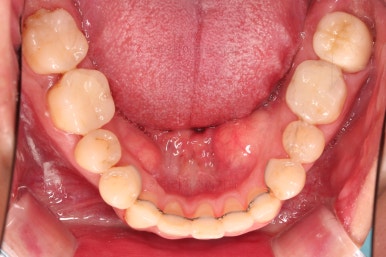

6. 마무리와 치료종료

부산구순구개열교정 종료 시의 입안의 모습입니다.

위아랫니 정렬이 잘 되었고, 치아 갯수가 위아래가 다르지만 교합도 나쁘지 않게 마무리가 되었습니다.

대문니 2개가 예후가 안좋긴 하나 양옆 치아들과 유지철사로 부착해 두어 최대한 오래 조심히 써보기로 했습니다.

7. 전후 비교사진

치열이 정렬이 잘 되었고요.

웃을 때 보이는 치열의 느낌, 얼굴과의 조화 등 모든 부분이 좋아졌습니다.